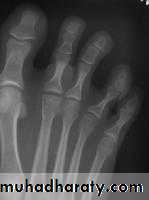

Examples of crushing Osteochondritis are Freiberg's diseases of the metatarsal ; Kohler's disease of the navicular ; Kienbock's disease of the carpal lunate ; Panner's disease of the capitulum and Scheuermann's disease (vertebral Osteochondritis ).